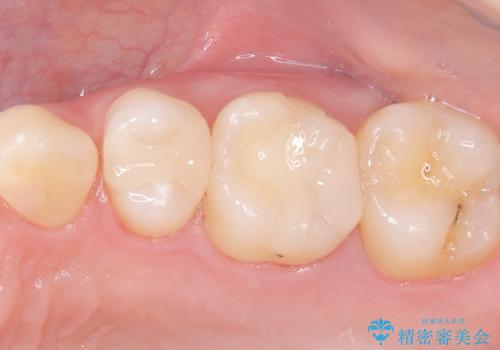

治療では、まず虫歯に侵された歯質を丁寧に除去し、セラミッククラウンを装着するための歯の形成を行いました。型取りから患者様の歯の形や色に合わせたオーダーメイドのセラミッククラウンを作製。セラミックは、隣接する歯との隙間なく精密に適合し、プラークが付着しにくいため、虫歯の再発を防ぐ効果があります。最終的に、精度の高いクラウンを装着し、咬み合わせを細かく調整しました。これにより、虫歯の再発を防ぎ、快適に食事ができる奥歯を取り戻していただけました。